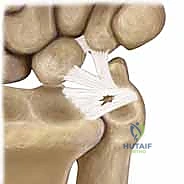

* Class 1B: Ulnar Avulsion. This is an avulsion of the peripheral aspect of the TFCC from its insertion onto the distal ulna. It can occur as a pure soft tissue avulsion or be associated with an ulnar styloid fracture. This type of injury directly disrupts the stabilizing effect on the DRUJ, leading to clinical instability. These peripheral tears are typically well-vascularized and amenable to repair.

* Class 1C: Distal Avulsion (Ulnocarpal Ligament Tear). This represents an avulsion of the TFCC's attachment to the ulnar carpus, specifically through disruption of the ulnolunate and ulnotriquetral ligaments. These lesions lead to ulnar carpal instability, often with volar translocation of the carpus.